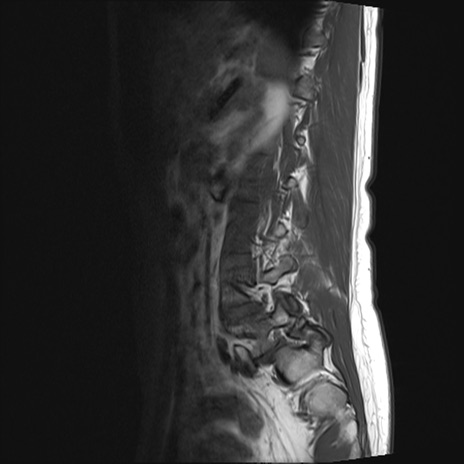

腰椎MRI

STIR(矢状断像)